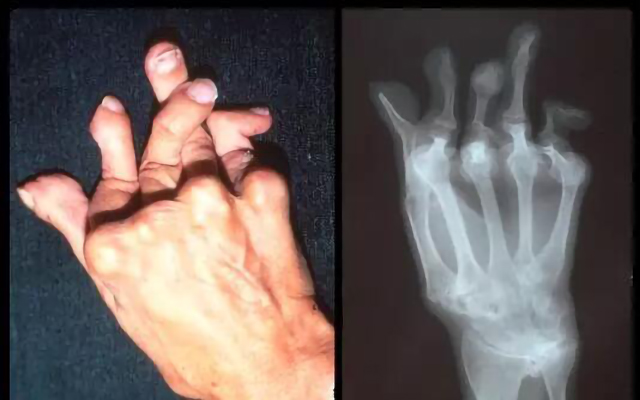

風(fēng)濕病是因?yàn)闄C(jī)體免疫功能紊亂而導(dǎo)致的全身性疾病,可損及關(guān)節(jié)、肌肉、內(nèi)臟等多個(gè)靶器官,關(guān)節(jié)是常見(jiàn)也是受累多的部位,由于多樣復(fù)雜的發(fā)病因素和受治療技術(shù)、治療條件的限制,大多數(shù)患者因?yàn)闆](méi)有條件接受系統(tǒng)、規(guī)范的治療,病情得不到有效控制而終導(dǎo)致身體殘疾。據(jù)國(guó)家衛(wèi)健委統(tǒng)計(jì),目前我國(guó)風(fēng)濕病患者數(shù)量約為2.5億人,重癥患者有8000萬(wàn)人,其中約有53%的患者因疾病導(dǎo)致肢體殘疾,因此風(fēng)濕病被醫(yī)學(xué)界稱之為“頭號(hào)致殘疾病”。

圖:類風(fēng)濕導(dǎo)致手指殘疾